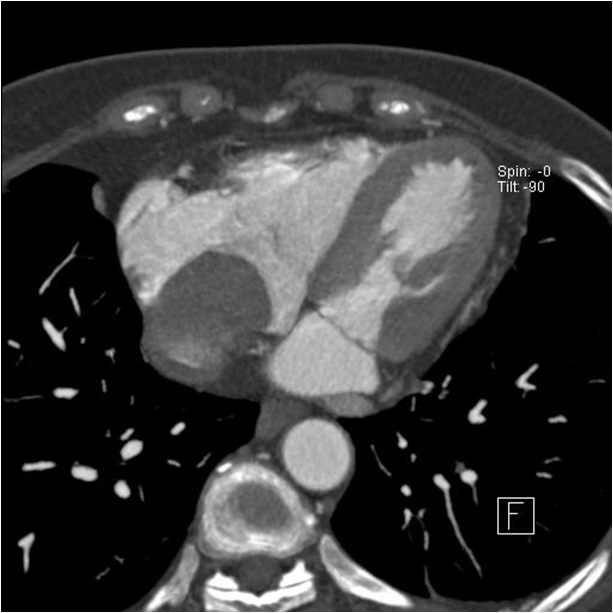

cardiomegaly on x-ray 11/F

Kyungsun Nam, Department of Radiology, Yonsei University College of Medicine

HIT : 16